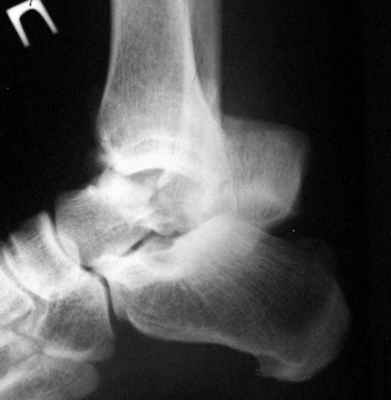

Перелом шейки тарана с вывихом блока |

Мужчина 30 лет поступил через неделю после травмы (оступился в яму при ходьбе) с вывихом блока тарана и оскольчатым переломом шейки.Снимок в приложении. Учитывя высокий риск аваскулярного некроза блока, что предпочесть? Открытая репозиция с фиксацией винтами? Плюс артродез смежных суставов? Удаление смещенного отломка формирование берцово-пяточного блока с удлинением голени? Заранее спасибо.